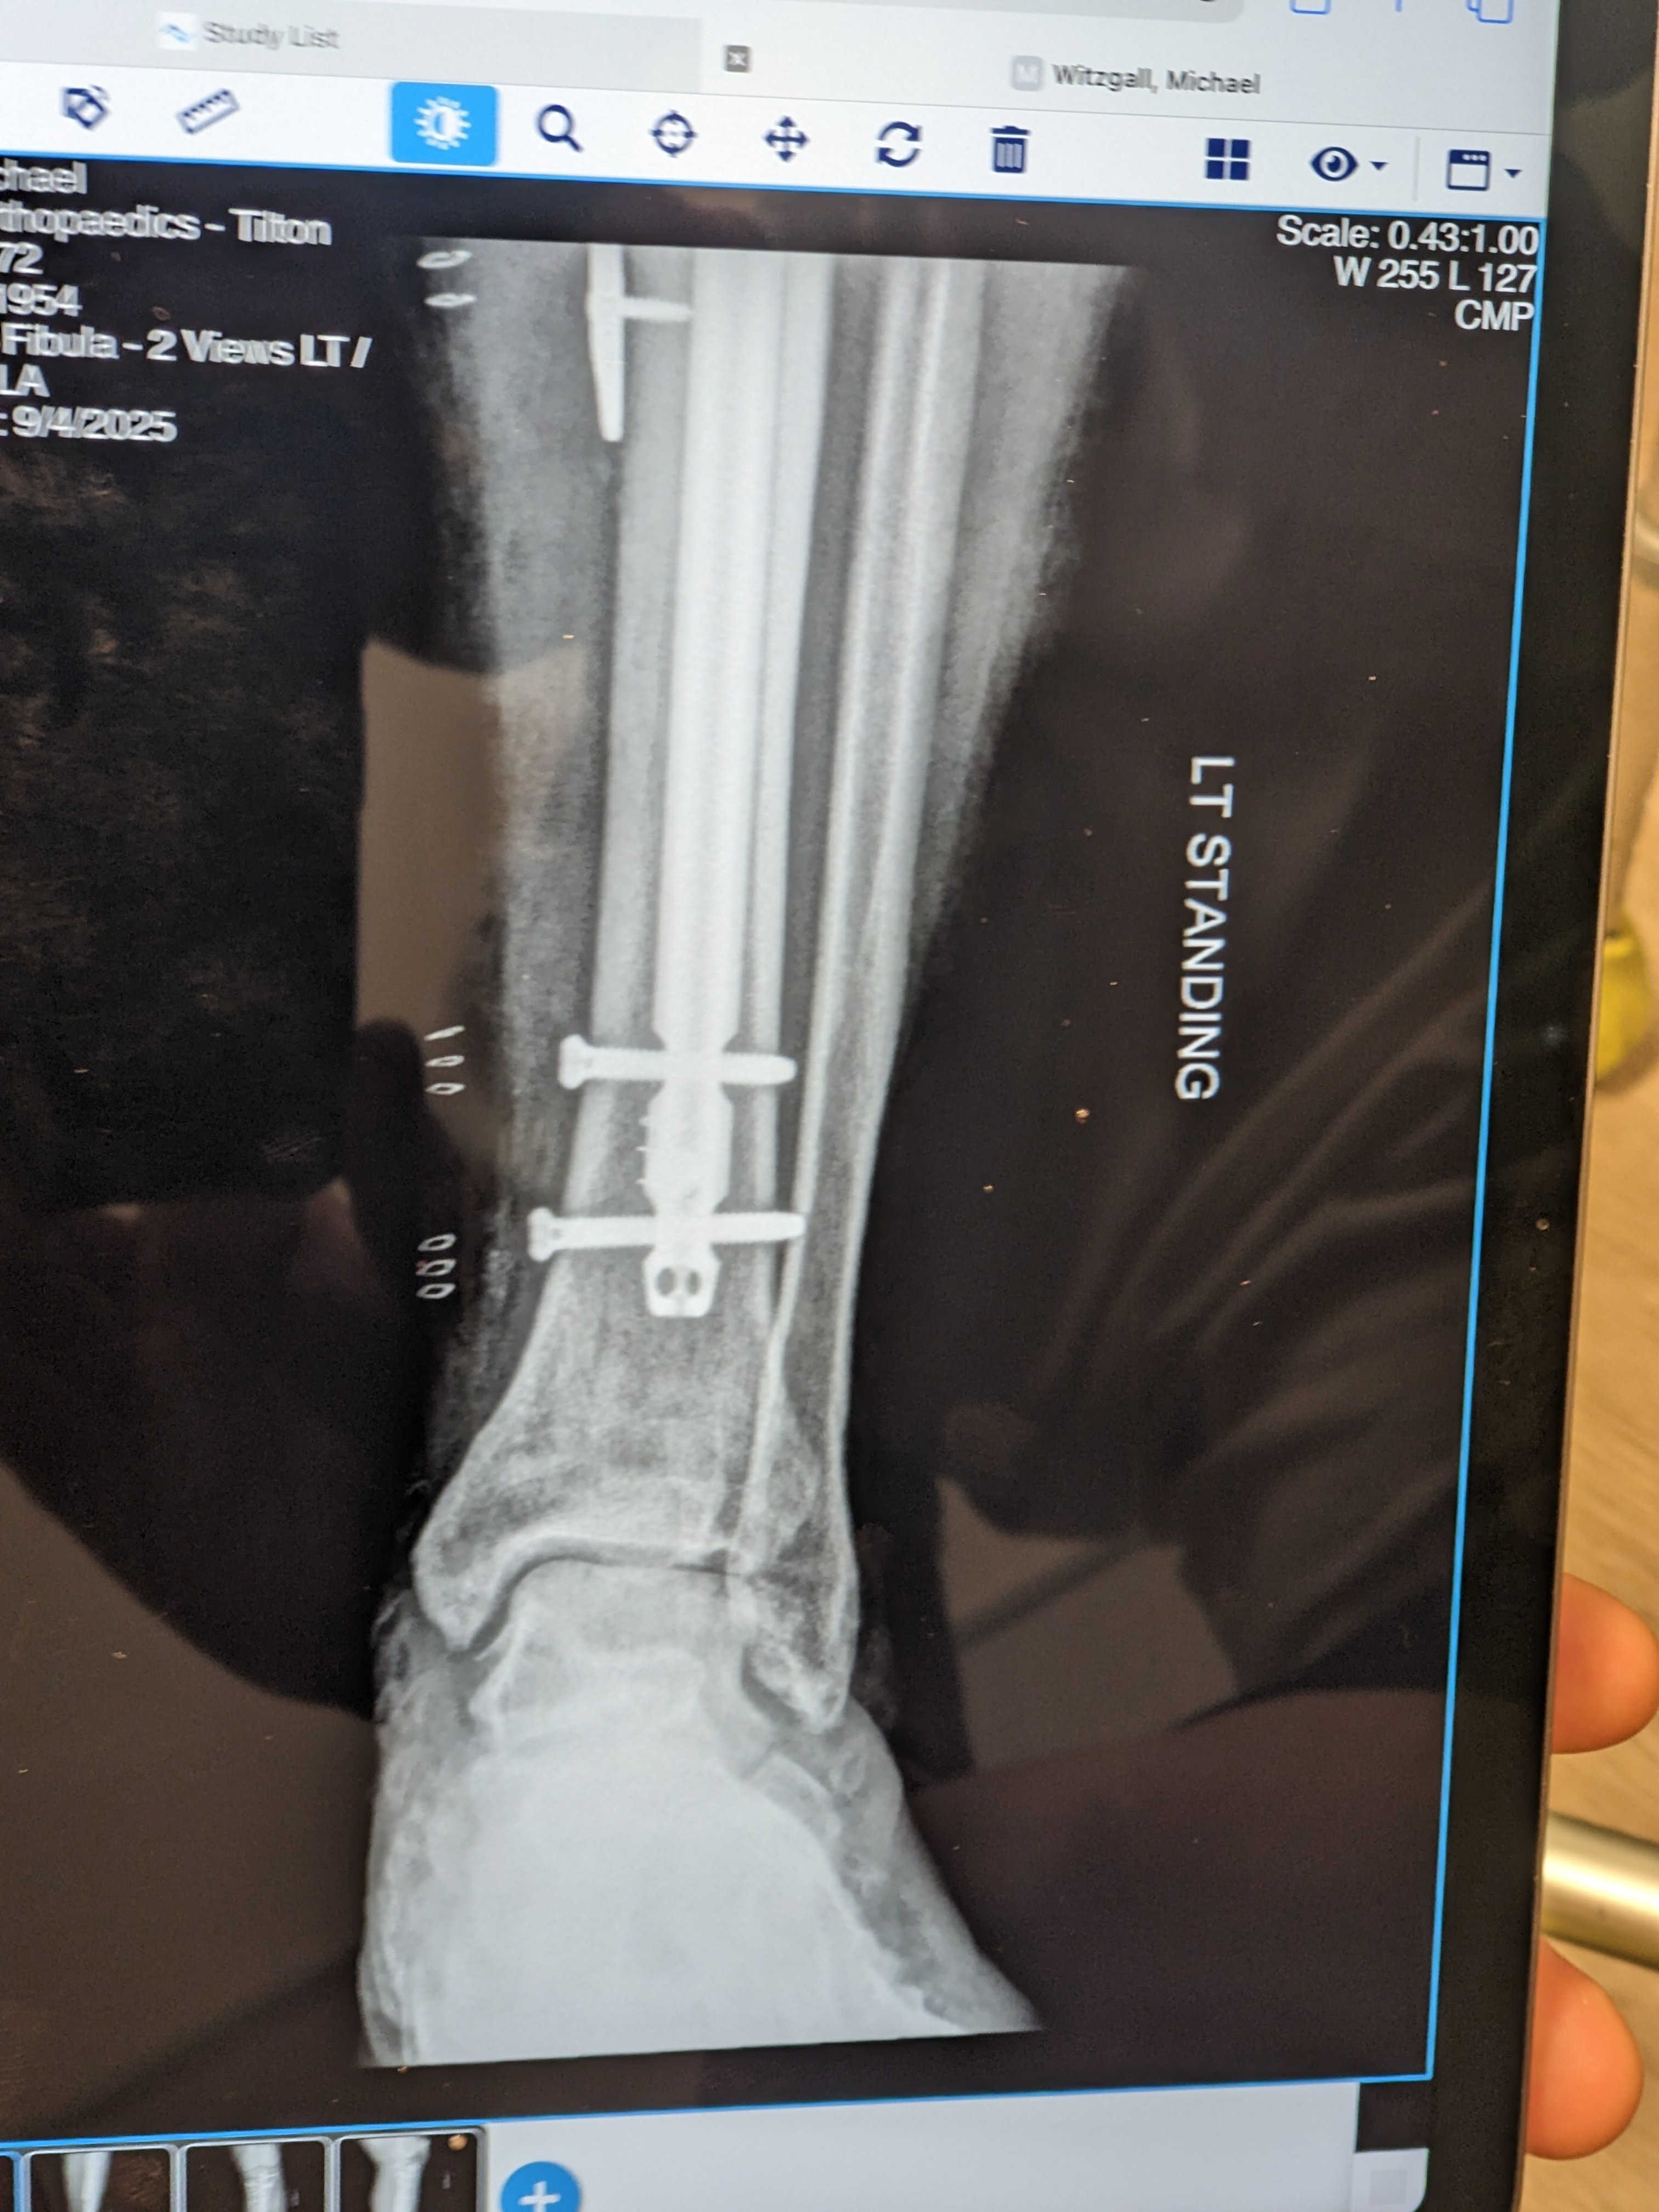

I got my original hardware back that was removed and replaced with the Superduty stuff. I wonder if these items can be resold to third world regions in need of medical implants?

New hardware is providing more stability. Now only hope the crunched Tibia begins to mend.